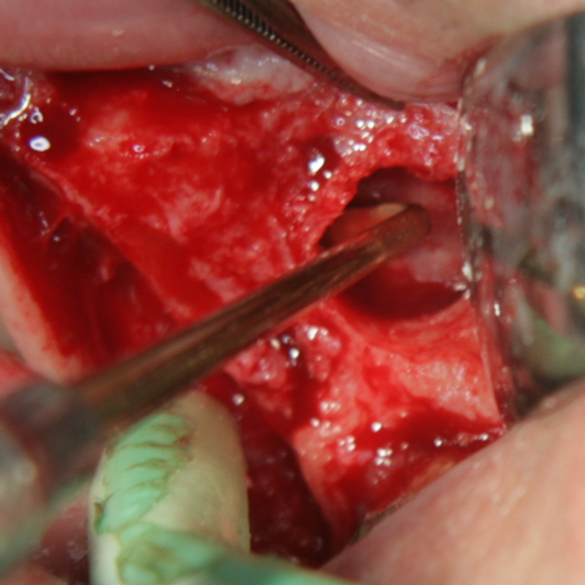

Отворен максиларен синус в началото на интервенцията. Случаят е интересен със следното - твърде атипична форма на трепанационния отвор. На какво се дължи на това - на лошо планиране на оперативния достъп или на нещо друго? Дължи се на факта, че отначало въпросната намеса беше планирана като балонен синуслифт; за съжаление обаче мембраната на синуса се разкъса и надуването на балона стана невъзможно.